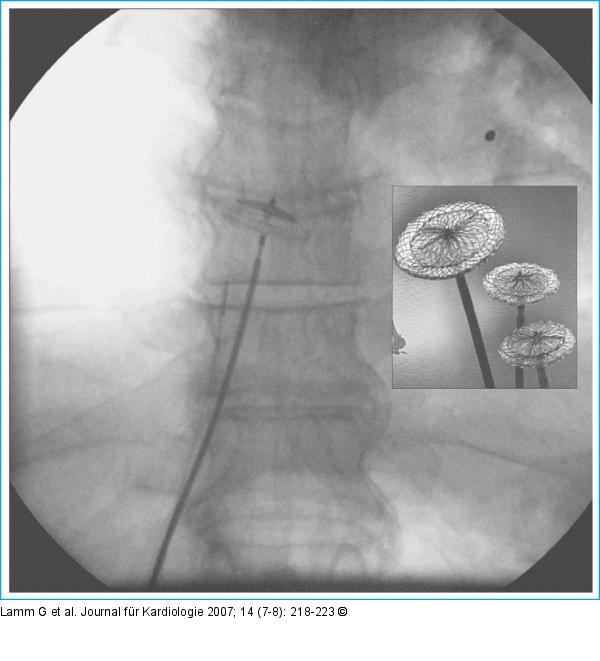

Abbildung 1: Amplatzer-Okkluder Ampaltzer-PFO-Okkluder - Plazierung unter Röntgensicht |

Abbildung 1: Amplatzer-Okkluder

Ampaltzer-PFO-Okkluder - Plazierung unter Röntgensicht |